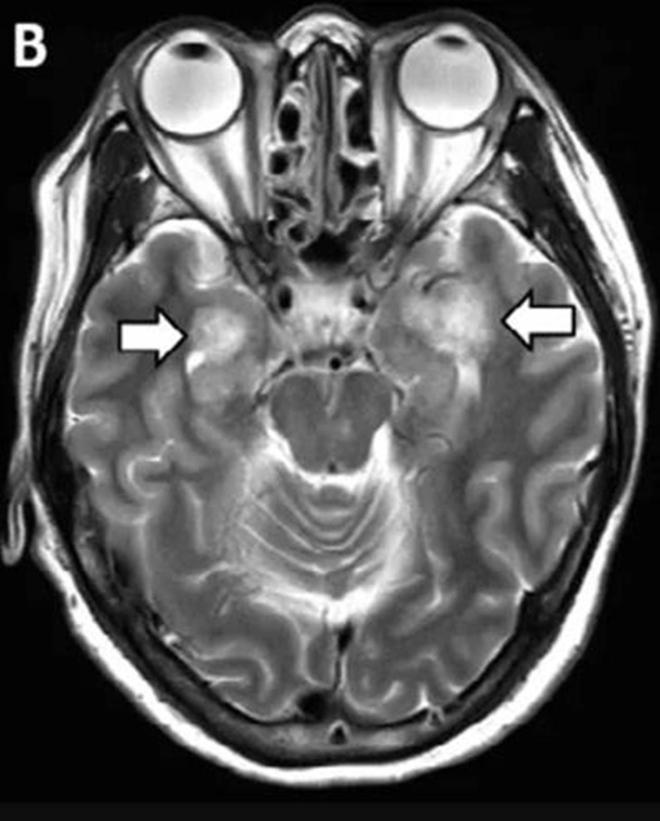

Pacientes con ACV y convulsiones

Estudios científicos revelan que la pérdida de los sentidos del olfato y el gusto son malas señales, ya que son considerados síntomas del coronavirus sospechosos. Pero además un porcentaje de pacientes con COVID-19 han presentado algunos problemas neurológicos, tales como los ACV y en algunos casos confusión mental.